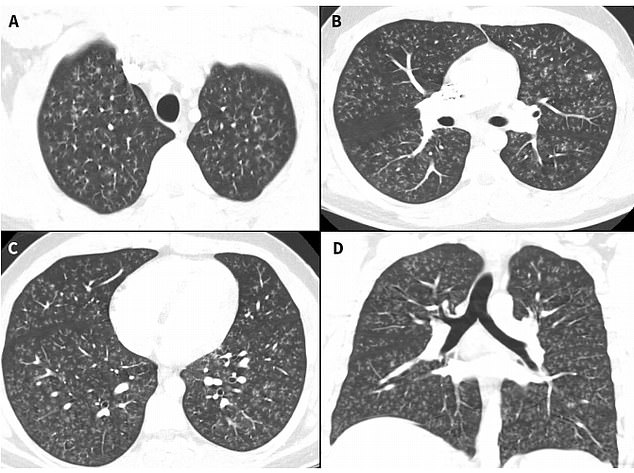

爆米花肺